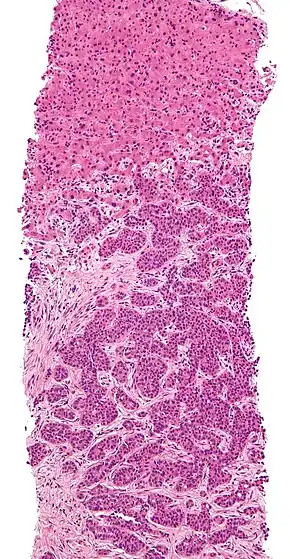

Squamous cell carcinoma occluding bronchus with metastasis to adjacent lymph node.

The cells in a metastatic tumor resemble those in the primary tumor. Once the cancerous tissue is examined under a microscope to determine the cell type, a doctor can usually tell whether that type of cell is normally found in the part of the body from which the tissue sample was taken.

For instance, breast cancer cells look the same whether they are found in the breast or have spread to another part of the body. So, if a tissue sample taken from a tumor in the lung contains cells that look like breast cells, the doctor determines that the lung tumor is a secondary tumor. Still, the determination of the primary tumor can often be very difficult, and the pathologist may have to use several adjuvant techniques, such as immunohistochemistry, FISH (fluorescent in situ hybridization), and others. Despite the use of techniques, in some cases the primary tumor remains unidentified.